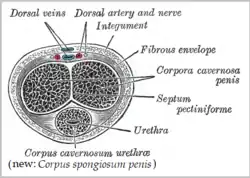

| spongy urethra (or penile urethra) | Runs along the length of the penis on its ventral (underneath) surface. It is about 15 to 25 cm in length,[9] and travels through the corpus spongiosum. The ducts from the urethral gland (gland of Littré) enter here. The openings of the bulbourethral glands are also found here.[10] Some textbooks will subdivide the spongy urethra into two parts, the bulbous and pendulous urethra. The urethral lumen runs effectively parallel to the penis, except at the narrowest point, the external urethral meatus, where it is vertical. This produces a spiral stream of urine and has the effect of cleaning the external urethral meatus. The lack of an equivalent mechanism in the female urethra partly explains why urinary tract infections occur so much more frequently in females. | Pseudostratified columnar – proximally, Stratified squamous – distally |

Position of the urethra in males Transverse section of the penis

Transverse section of the penis Male urethral opening on glans penis